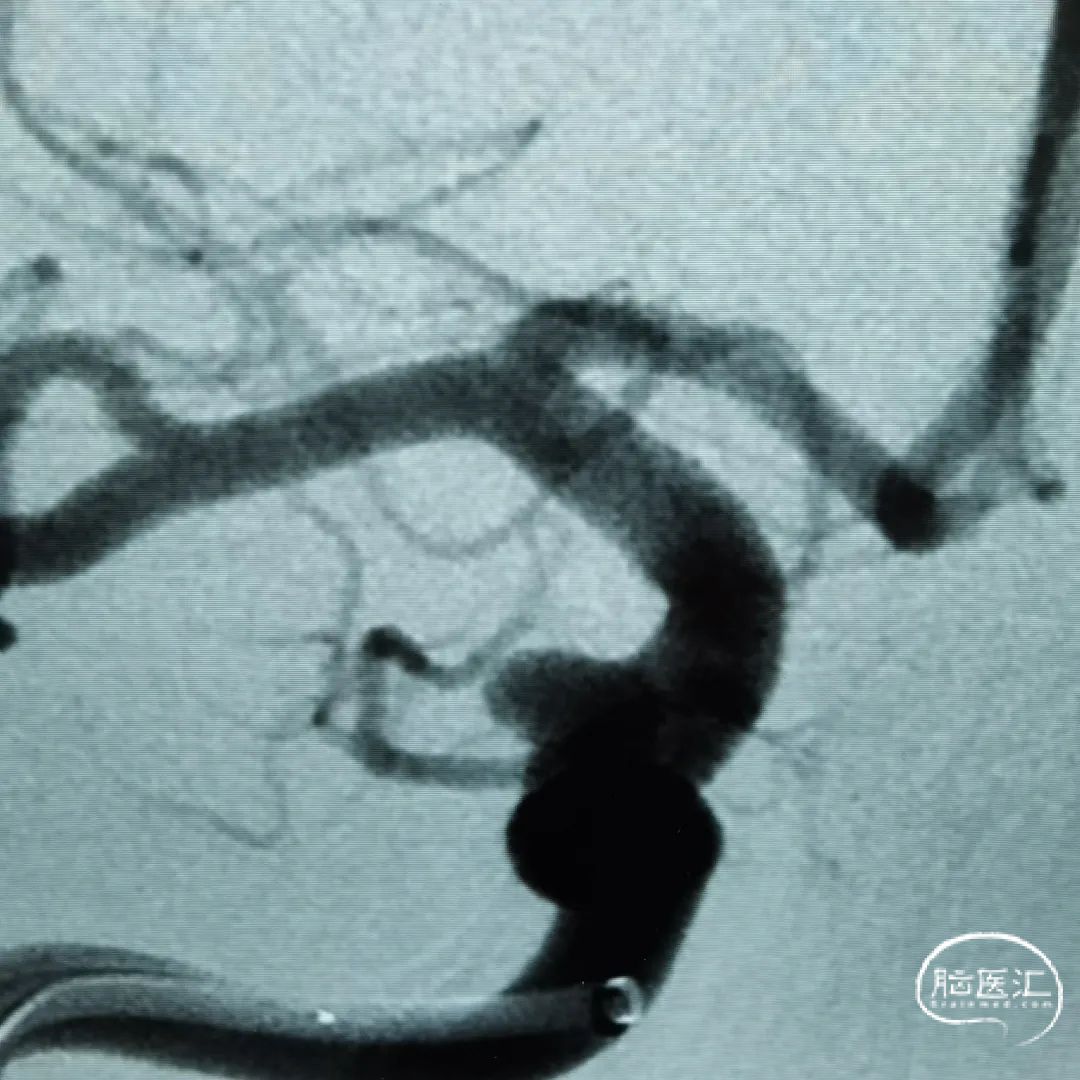

这是一根通桥银蛇DA远端通路导引导管,在Sim II和导丝到位后,通桥银蛇DA远端通路导引导管能够非常容易地顺着架设的道路直接放到位,然后进行后续使用Pipeline血流导向密网支架来治疗复发动脉瘤的操作。我们可以看到在Pipeline的到位以及释放的过程中,通桥银蛇DA远端通路导引导管都非常稳定,能够获得比较满意的结果。

释放PED过程中,通桥银蛇DA远端通路导引导管头端非常稳定。

术前

术后